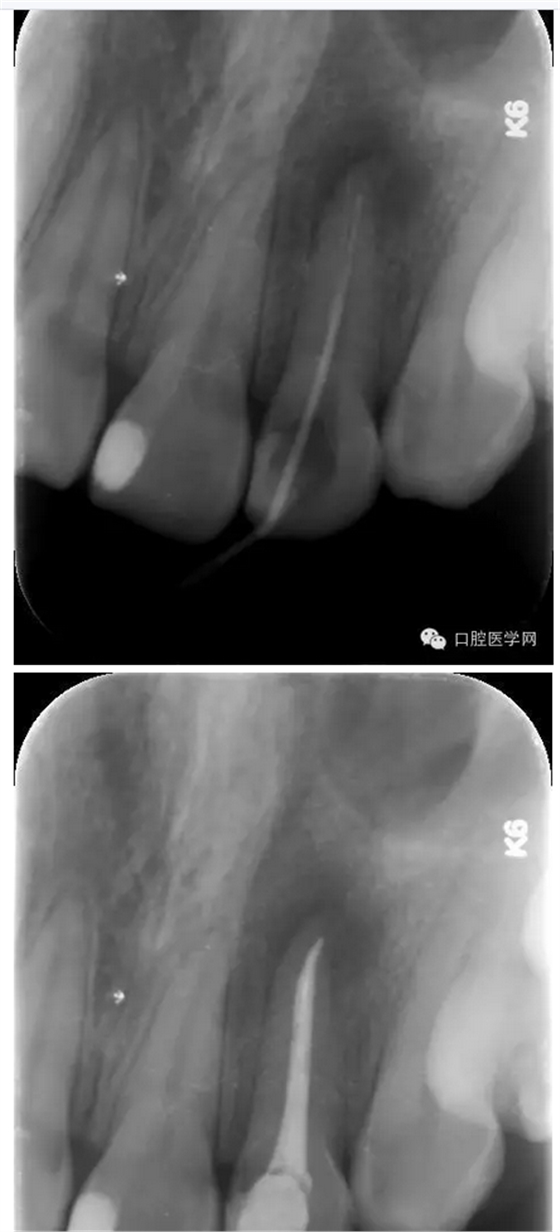

檢查:22舌側(cè)可見牙色充填體,牙冠變色,松動1度,叩診(++),唇側(cè)齦頰溝變淺,捫診疼痛,冷熱測無反應(yīng)。

X線片:示22已行根管治療,治療不完善,根尖區(qū)可見約0.5*0.5mm密度減低區(qū),牙周膜影略增寬。

治療:第一次:去舊充填體,去腐質(zhì),GG鉆去除牙膠充填體,疏通根管,測量工作長短,H銼與K銼去除剩余牙膠,雙氧水和鹽水大量沖洗,機擴(kuò)至S1,超聲蕩洗,激光行根管消毒,封CP球。

第二次:復(fù)診無不適,回去后疼痛即刻解除。叩診無不適。無松動。處置:去暫封,見根管內(nèi)無滲出,機擴(kuò)至F2,雙氧水和鹽水大量沖洗,超聲蕩洗,激光蕩洗加消毒,干燥,封氫氧化鈣。

第三次:復(fù)診無不適。叩診無不適,無松動。處置:去除暫封物,鹽水沖洗,試尖,牙膠尖+AHplus糊劑冷測壓充填,玻璃離子體充填。